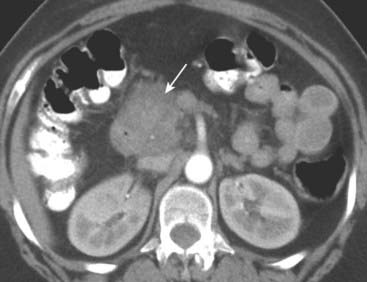

image

Figure 18-10 Key findings on CT of the GI tract.

Findings applicable to any part of the bowel and key to the diagnosis of bowel abnormalities on CT. A, There is thickening and enhancement of the wall of the bowel (circle). When distended, as these loops of large bowel are, the bowel wall is normally very thin. B, There is submucosal infiltration of the wall (thumbprinting) (solid white arrow). In this case of ischemic colitis, it most likely represents edema with some hemorrhage. C, Infiltration of the surrounding fat is seen (dotted white arrow), a sentinel finding that usually heralds adjacent inflammation. There is also extraluminal air (circle), a sign of bowel perforation.